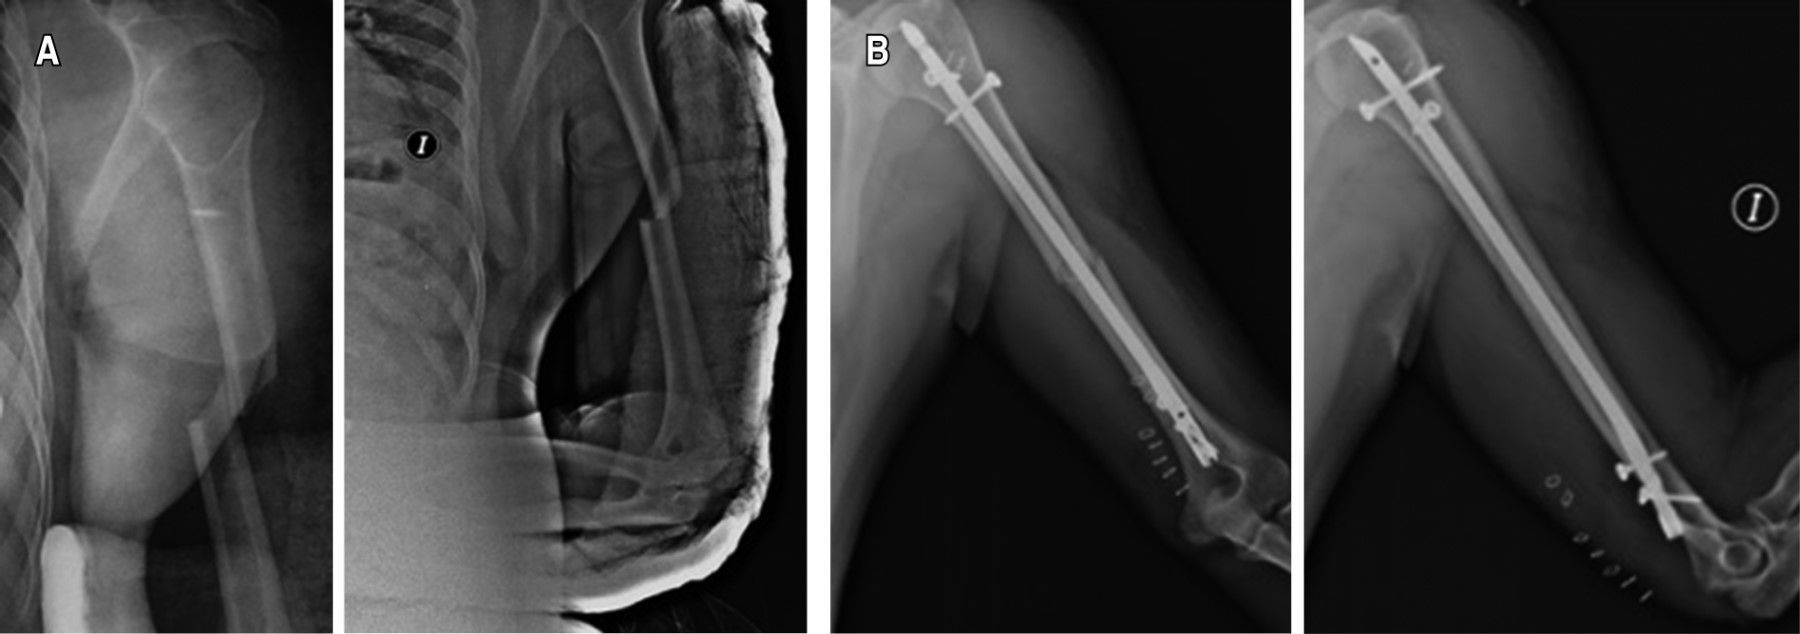

The treatment of shaft fractures of the humerus to this day is still controversial. Humeral intramedullary nailing (HIN) is emerging as the gold standard for the treatment of this type of fracture. In the antegrade technique, the access allows direct entry to the proximal humerus epiphysis, with the disadvantage of involving a healthy joint, generating chronic pain or the need for revision surgeries. The retrograde technique eliminates the risk of postoperative shoulder pain, rotator cuff injury and axillar nerve injury. It is more complex since the entry point is a thin layer of bone, generating an iatrogenic fracture as the main complication. We present a 28-year-old male, run over, with a direct contusion on the left arm. He began with severe pan, deformity, increased volume and loss of function, going to the emergency department at Hospital Ángeles Mocel for evaluation and treatment. Radiographically with a simple transverse fracture in the middle third of the humerus. He undergoes definitive treatment with retrograde HIN. On the seventh postoperative day, he presents full range of motion in shoulders and elbows, with pain in the approach area.

Figure 1

Figure 2